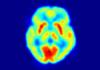

Tehran, Dec. 23 (MNA) – Researchers at Amir Kabir University of Technology have made use of a toxic substance as a way to increase the resolution of images taken from cancerous tumors; taking another step toward the production of anti-cancer drugs.

He added that this substance has marked indirectly by technetium m99 and, using a chelator, a precision agent for cancer imaging was prepared.

Pointing to the applications of the findings, Mohammad Bagheri said that the accumulation of this substance in cancerous tumors facilitates imaging with high resolution.